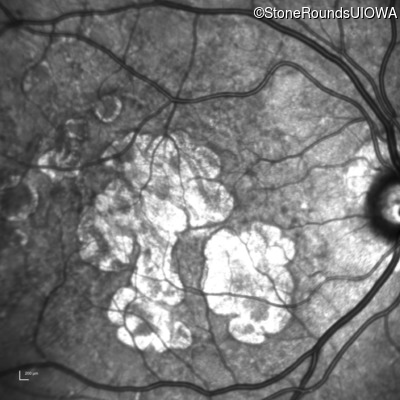

Infrared Fundus Photograph - Right - 20/25

Exemplar

Infrared Fundus Photograph - Left - 20/25 -2

Blue Autofluorescence - Right - 20/25